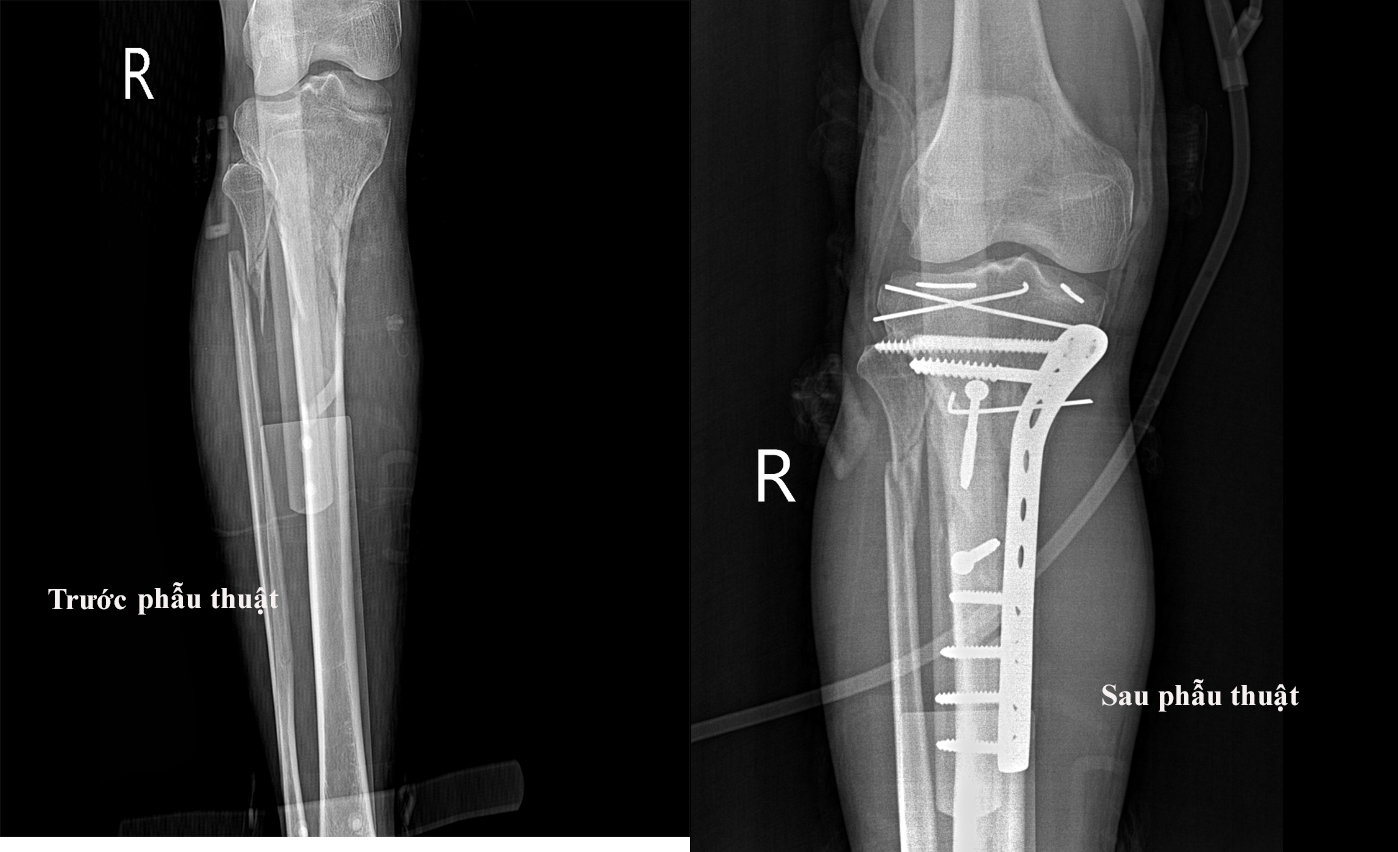

Qua thăm khám, tại 1/3 trên mặt trước ngoài cẳng chân phải cảu bệnh nhân bị biến dạng có vết thương hở kt ~3cm lộ xương, chảy máu, không đi lại được. Chụp Xquang xương cẳng chân thẳng nghiêng hình ảnh cho thấy gãy phần trên hai xương cẳng chân, gãy hở độ I; Vỡ mâm chày. Bệnh nhân được chỉ định mổ cấp cứu.

Trong quá trình phẫu thuật, các bác sĩ phát hiện mâm chày ngoài vỡ lún. Các bác sỹ tiến hành làm sạch ổ gãy, đẩy mâm chày trong về bình diện giải phẫu, kết hợp xương bằng 02 đinh kischner. Tiếp tục rạch da mặt trong tách tổ chức dưới da, qua các lớp cân cơ, cắt sụn chêm ngoài bộc lộ ổ gẫy. Qua kiểm tra: mâm chày trong gẫy thành nhiều mảnh nhỏ, lan xuống thân xương, kíp mổ tiến hành làm sạch ổ gãy, đặt lại các mảnh xương theo bình diện giải phẫu kết hợp xương bằng 01 nẹp 12 lỗ, 8 vít.

Bệnh nhân đã được kiểm tra sau kết hợp mâm chày, xương chày phải, hiện tại hai xương thẳng trục. Do ổ gãy nhiều mảnh rời phức tạp nên bệnh nhân phải mất thời gian dài để ổn định.

Hình ảnh chụp XQ của bệnh nhân trước và sau phẫu thuật